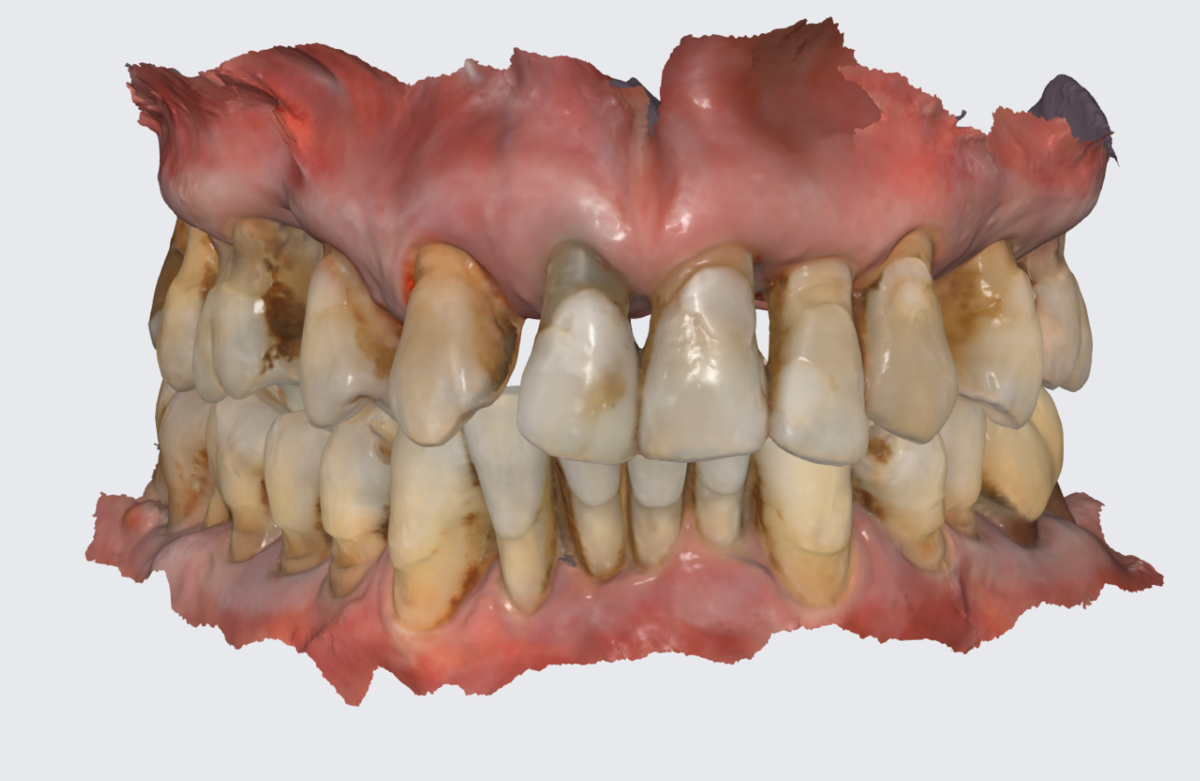

Прикус. Мезиальный. Нижняя челюсть впереди верхней.

Мезиальный прикус.

Собственные зубы и кость пациентов с мезиальным прикусом приспособились вот к такой жизни - зоны роста как бы выдвинуты. Ох, ну и оборот, но как ещё объяснить? Наклон имеют зубы, наклон имеет кость, в которой эти зубы находятся.

Боковой срез.

Сбоку - то же самое.

Поэтому, как только такие зубы будут удалены, зоны роста вернутся к естественному, природному положению - "встанут" ровно, плюс подвергнутся неминуемым процессам деструкции.

Как тогда ставить имплантаты? Хорошего ничего не будет. Одномоментно имплантировать? Зонам роста плевать, при удалении зуба останется "дырка" в кости, стенки костной лунки (кортикальные пластинки) будут слабы и зоны роста "уедут" - ничего их не остановит.

Поэтому план такой - НИКАКОГО МАССОВОГО удаления зубов:

1. Удаление зуба под номером 1 и консервация лунки. Ждём 4 месяца.

2. Удаление зуба под номером 2 и пластика собственной костью, взятой с бугра в/ч. Ждём приживления 4 месяца.

Зуб под номером 4 не столь интересен и время его удаления не буду расписывать. Как решит хирург, так и будет.

Таким образом мы сохраним максимально возможное количество кости. Ничего лучше, увы, не придумаешь.